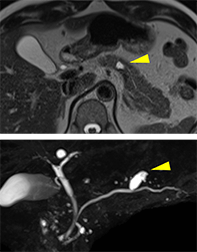

超音波内視鏡検とは、内視鏡の先端に取り付けられた超音波画像装置で、膵臓、胆嚢、胆管、リンパ節などの通常の腹部エコー、CT、MRIなどの検査で見にくい部位を調べることができる検査法です。

詳細な観察に関してはEUSが一番優れており、CTやMRIでは発見できないような小さな膵癌を発見することができます。

また、人間ドックなどの腹部超音波検査でよく発見される膵のう胞は腫瘍性のう胞である膵管内乳頭粘液性腫瘍(IPMN)であることが多いとされています。EUSではのう胞内結節などの悪性化を疑う所見を高感度に発見することができます。

膵尾部分枝型IPMN

超音波内視鏡のみでのう胞内結節を指摘

CT、MRIで膵管狭窄はある

が腫瘤は指摘できず

超音波内視鏡のみで

膵管狭窄部に膵腫瘤を指摘